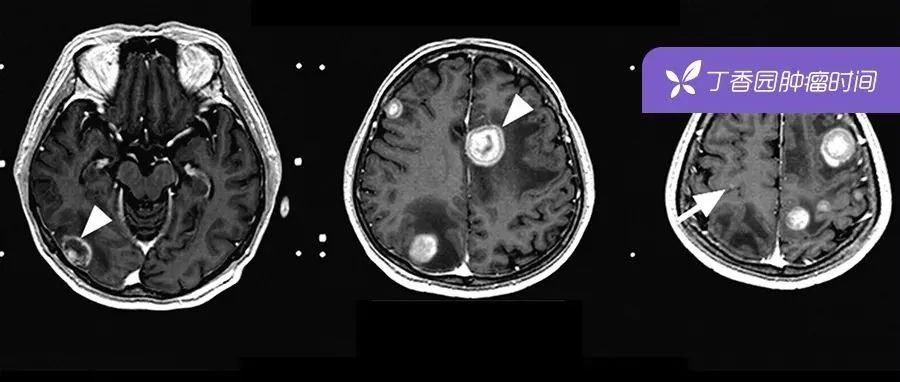

肺癌脑转移的 9 大治疗手段,最全总结都在这里!

肺癌脑转移患者的治疗选择越来越多,生存时间得以延长。但发生率高、预后差、自然生存时间短的现状仍未改变。如何选择治疗策略是临床工作的一大难点?本文结合治疗指南整理了肺癌脑转移的各种治疗策略。62 岁男性,左肺非小细胞肺癌,幕上和幕下室多发转移,并伴有病灶周围水肿,无神经症状。1肺癌脑转移发病情况肺癌脑转移发生率明显高于黑色素瘤、乳腺癌、肾癌和结直肠癌,20%~65% 的肺癌患者在病程中会发生脑转移,是脑转移性肿瘤中最常见的类型。...